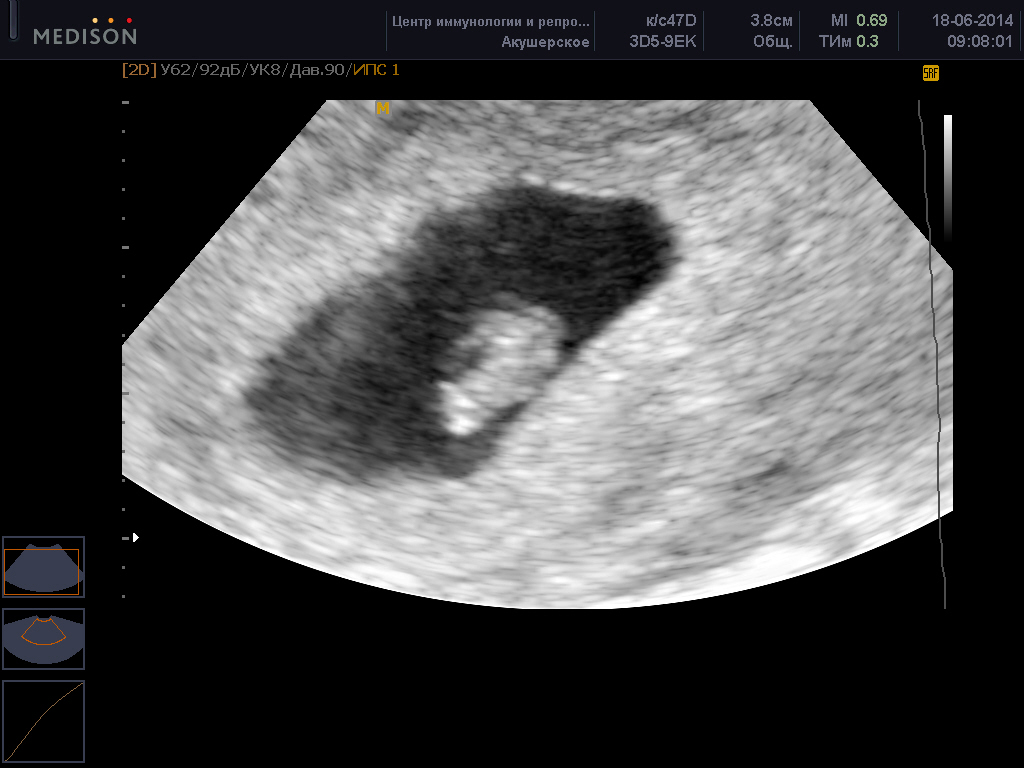

УЗИ фото при беременности, фото плода 1 триместр 5-12 недель, 3д узи фото

8 недель